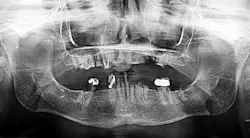

Mary is a 42-year-old patient who had gastric bypass surgery for excessive weight five years prior to seeing me. She has suffered from multiple digestive ailments, including an inability to maintain a healthy body mass, since the surgery. Mary’s oral system is in dysfunction (figure 3), and she was referred to me by her digestive specialist in hopes of improving her ability to chew efficiently.

Mary is suffering from severe dental dysfunction. Of her 18 remaining teeth only three on her lower arch protrude through her gum tissue, and those teeth are severely decayed and functional. She is suffering from multiple chronic infections surrounding the remaining tooth fragments. On a positive note, Mary has adequate lower jaw bone to support a temporary fixed implant-supported bridge to be placed at the time of tooth extraction, and her upper jaw bone can be repaired with bone grafting at the time of tooth extraction, followed by implant placement after sufficient bone healing.